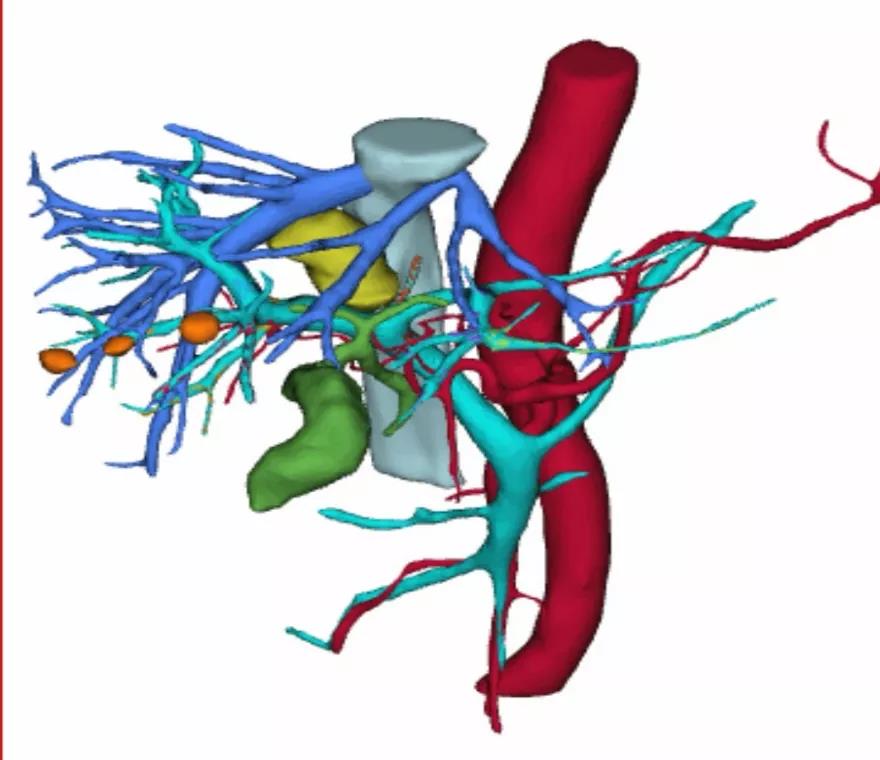

依据三维检查结果确定手术方案依据三维检查结果确定手术方案

三维成像结果出来后,证实了“肿块虽紧邻周围重要血管组织,但仍有机会可以完整切除肝脏肿块”的判断。经与病人及家属商量后,确定“行开腹探查,根据术中情况争取肝脏肿块根治性切除,若术中无法切除,再术中行肝肿瘤微波消融治疗”的方案。